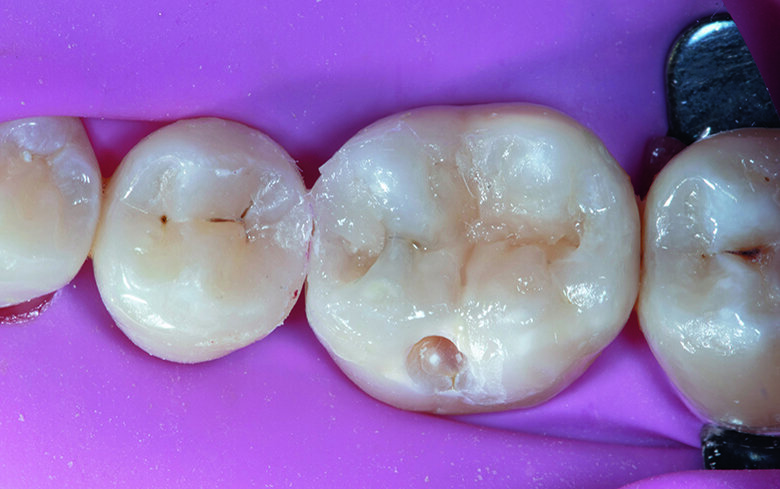

Tooth #45 was restored first to help increase visibility during restoration of tooth #46. As the cavity on the premolar was a shallow proximal box, horizontal incremental layering was used with Shofu range of Bioactive composites, Beautifil Injectable XSL, shade A2 (Self-leveling composite resin) injected in small quantity followed by Beautifil II LS, shade A2 (packable composite) in snow-plow technique. In the final increment the marginal ridge and distal pit area were carved to achieve a more natural occlusal morphology (Fig. 4).

The sectional matrix on premolar and ring were removed carefully with the help of artery forceps without dislodging the matrix band placed on molar. The band was burnished with light to medium pressure on the adjacent premolar tooth to ensure proper contour and contact (Fig. 5).